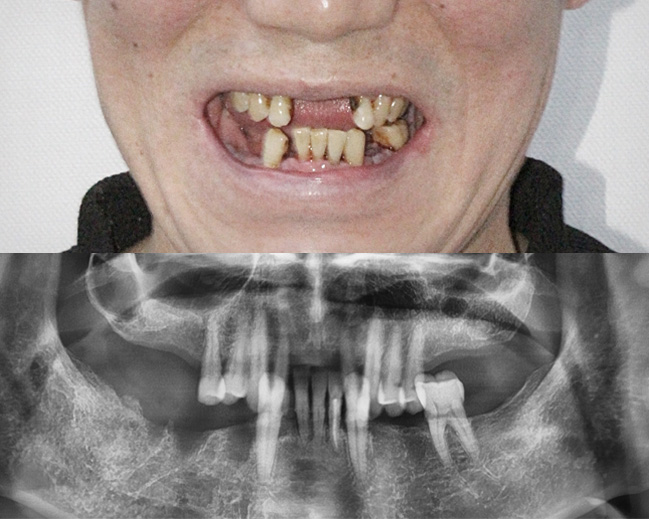

이갈이 / 턱관절 / 만성통증

23년 임상경험으로 쌓인 노하우를 바탕으로 원인을 명확히 파악하고,

그 원인에 따른 근본적인 치료 방법을 시행하여 이갈이와 턱관절 장애 고민에서 해방시켜드리겠습니다.